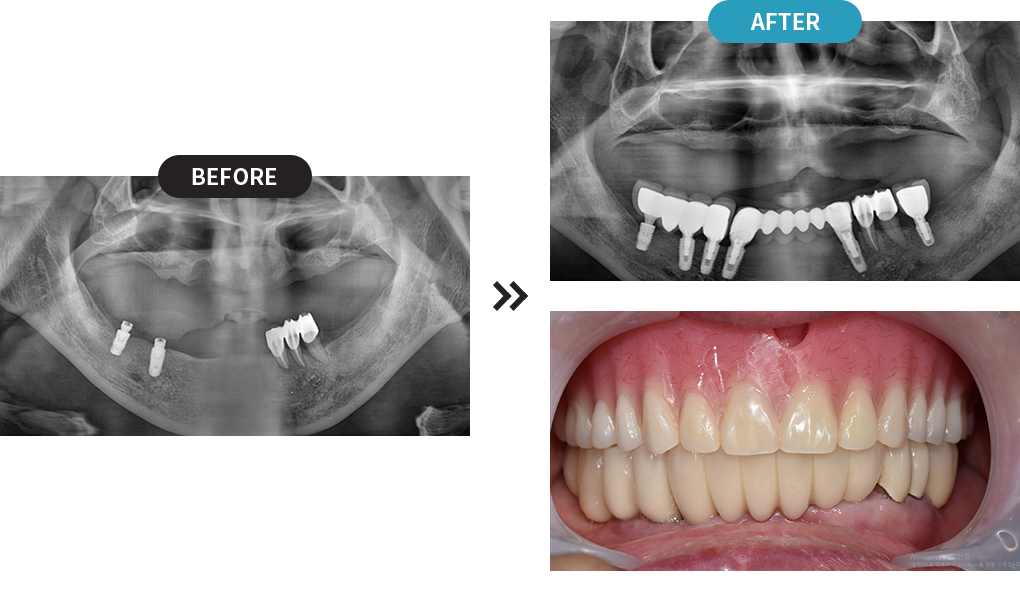

3D디지털 스캔을 활용하여 가장 안전하게 임플란트를

식립할 수 있는 위치를 0.1mm 오차까지 정확하게 계산합니다.

제작된 보철물을 모의 수술을 통해 정해진 임플란트 식립 위치에 빠르고 정확하게 식립합니다.